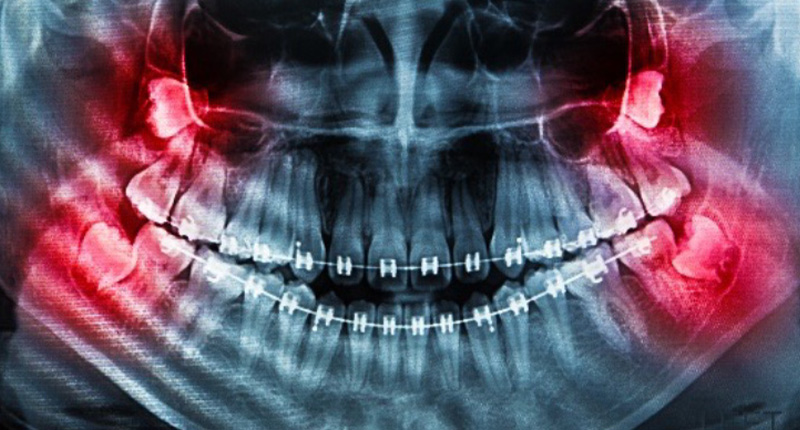

親知らずは永久歯がはえそろった後にはえてくる歯で、10代後半~20代前半ではえてくる方が多いです。とはいえ、もっと遅くにはえてくる方やはえてこない方もいらっしゃいます。はえていても中に埋まっていたり横向きだったりと、はえ方も人それぞれ。見えていなくても、レントゲンを撮るとどのような状態か確認できます。

上顎の親知らずの方が下顎よりも腫れにくいのですが、難しい抜歯になるほど治療後の腫れや痛みが増す傾向にあります。特に斜めにはえていたり横向きにはえてきている場合には、注意が必要です。治療後には大事な予定は避けたほうが良いでしょう。

親知らずが腫れる原因は、いくつかのケースが考えられます。 お口の中の状態はご自分ではなかなか確認できません。まして、親知らずは見ただけではどのような状態ではえているのか確認することも困難です。歯科医院でレントゲンでの確認が必要です。